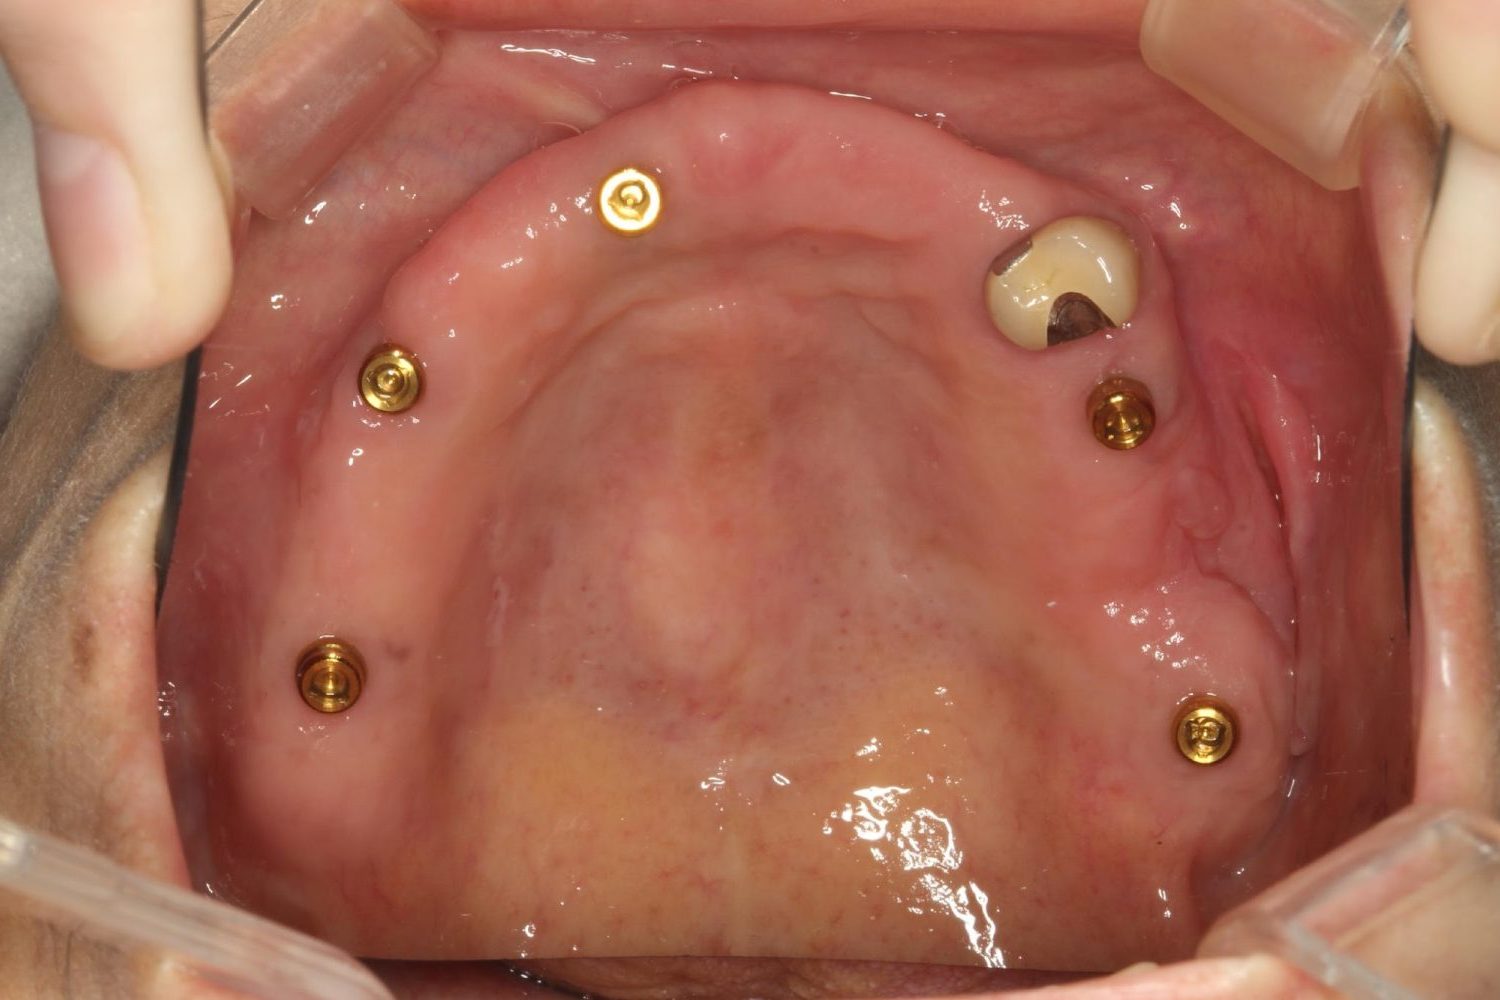

インプラント治療の症例紹介④

Before

After

主訴

義歯による疼痛

治療内容

下顎舌側に骨隆起があり義歯困難な状態。保存不可能な歯の抜歯を行い、インプラントを埋入し咬合再構成を行った。

治療費

2,851,200円(税込)

治療期間

29ヶ月

通院回数

26回

想定されたリスク

※咬合力の強い方なので、予防的にマウスピースの装着が必要。インプラント周囲炎の恐れがありました。

濱 仁隆先生

浜歯科

歯の欠損の対合歯の挺出等を修正し咬合平面を揃え咬合再構成を行った症例。